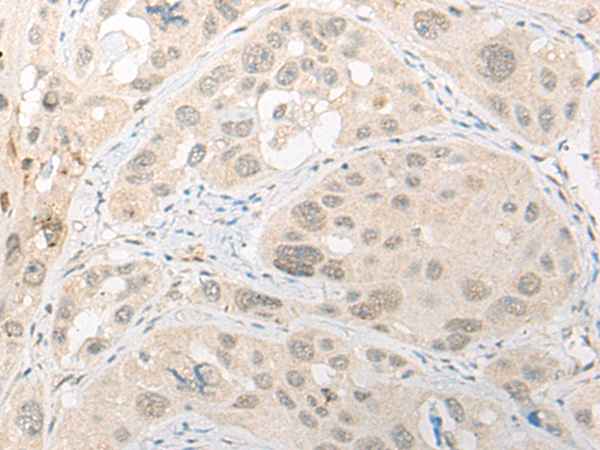

分类: 科研抗体货号: P13209别名: FCC1; COCA1; HNPCC; LCFS2; HNPCC1应用: WB,IHC反应种属: Human, Mouse